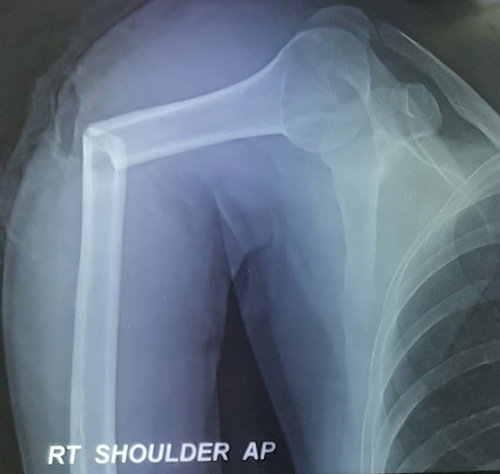

TSR (Total Shoulder Replacement) surgery performed on 80 yr old female with 4 part proxy humerus fracture following fall.

Reverse Shoulder Replacement